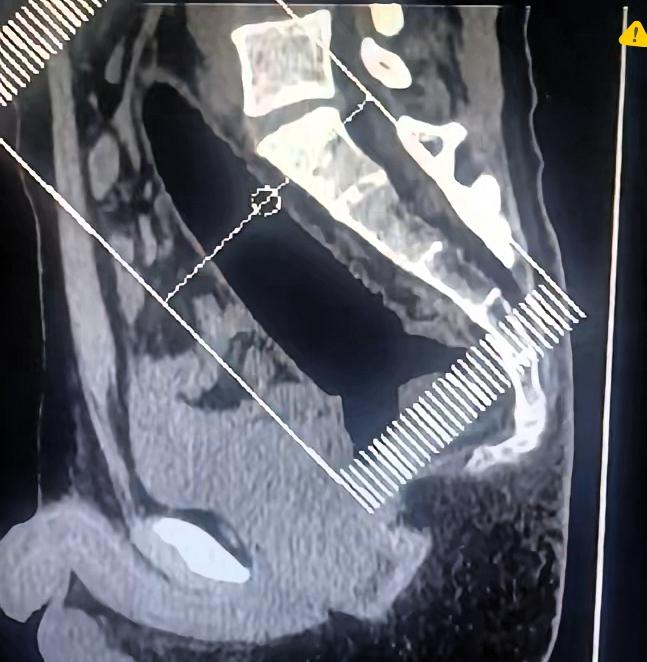

悲剧还是发生了! 一名男子因直肠内异物紧急就医,面对医生询问时却遮遮掩掩,不愿说出实情,直到检查后才发现,异物已经深入体内,长度更是让人后怕。 直肠里深入22厘米的异物,已经不是简单卡住,位置深、风险大,自己强行处理只会越陷越深,还可能划伤肠道。 不少人总抱着侥幸心理玩些危险操作,最后只能捂着屁股尴尬就医,看似离谱的事,在急诊室早已不是新鲜事。 很多人出事后不敢说实话,编各种理由搪塞,可身体不会骗人,一检查就能发现异物早已深入体内,不仅取出来难度极大,还随时可能戳破肠道引发严重感染。 别觉得这是小事,一旦肠道穿孔,腹膜炎、手术切除都是可能的后果,远比一时的尴尬可怕得多。 真正让人无奈的不是意外,而是明明可以避免,却非要拿健康冒险。 医生见多了各类情况,根本不会过多评判,隐瞒实情只会耽误治疗、加重风险。 健康从来经不起试探,别为了一时刺激拿身体开玩笑。 你觉得遇到这种情况,第一时间坦白是不是最明智的选择?